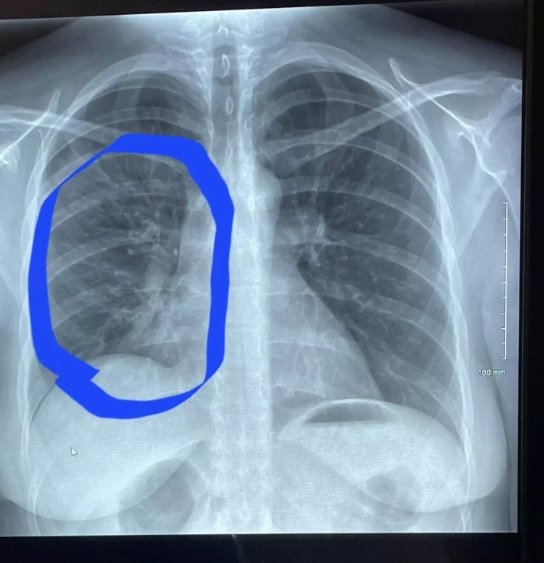

Roth returned to the medical clinic’s crisis office in Scott Area where specialists illuminated her she had an impediment in her right lung.

They said it was pneumonia,” she said. “It seems to be a tree with branches, it’s called ‘tree sprouting’ and it’s fundamentally the weakening of your lung.

The specialist showed Roth the sweeps of her lungs and brought up they didn’t seem as though they ought to for a 30-year-elderly person, however rather than somebody who had been ‘a smoker of a decade’.

“I seemed as though I had the lungs of somebody in their 80s, somebody a lot more established, when he showed me that first sweep.